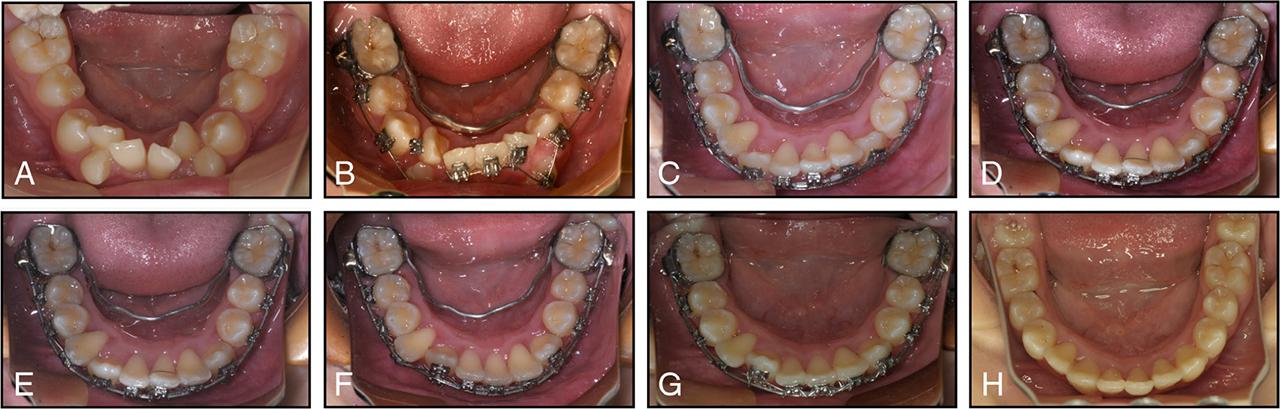

Figure 4